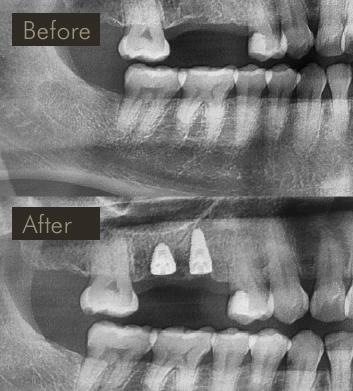

» X-ray image showing before & after placement of implants in upper right to replace 2 missing teeth.